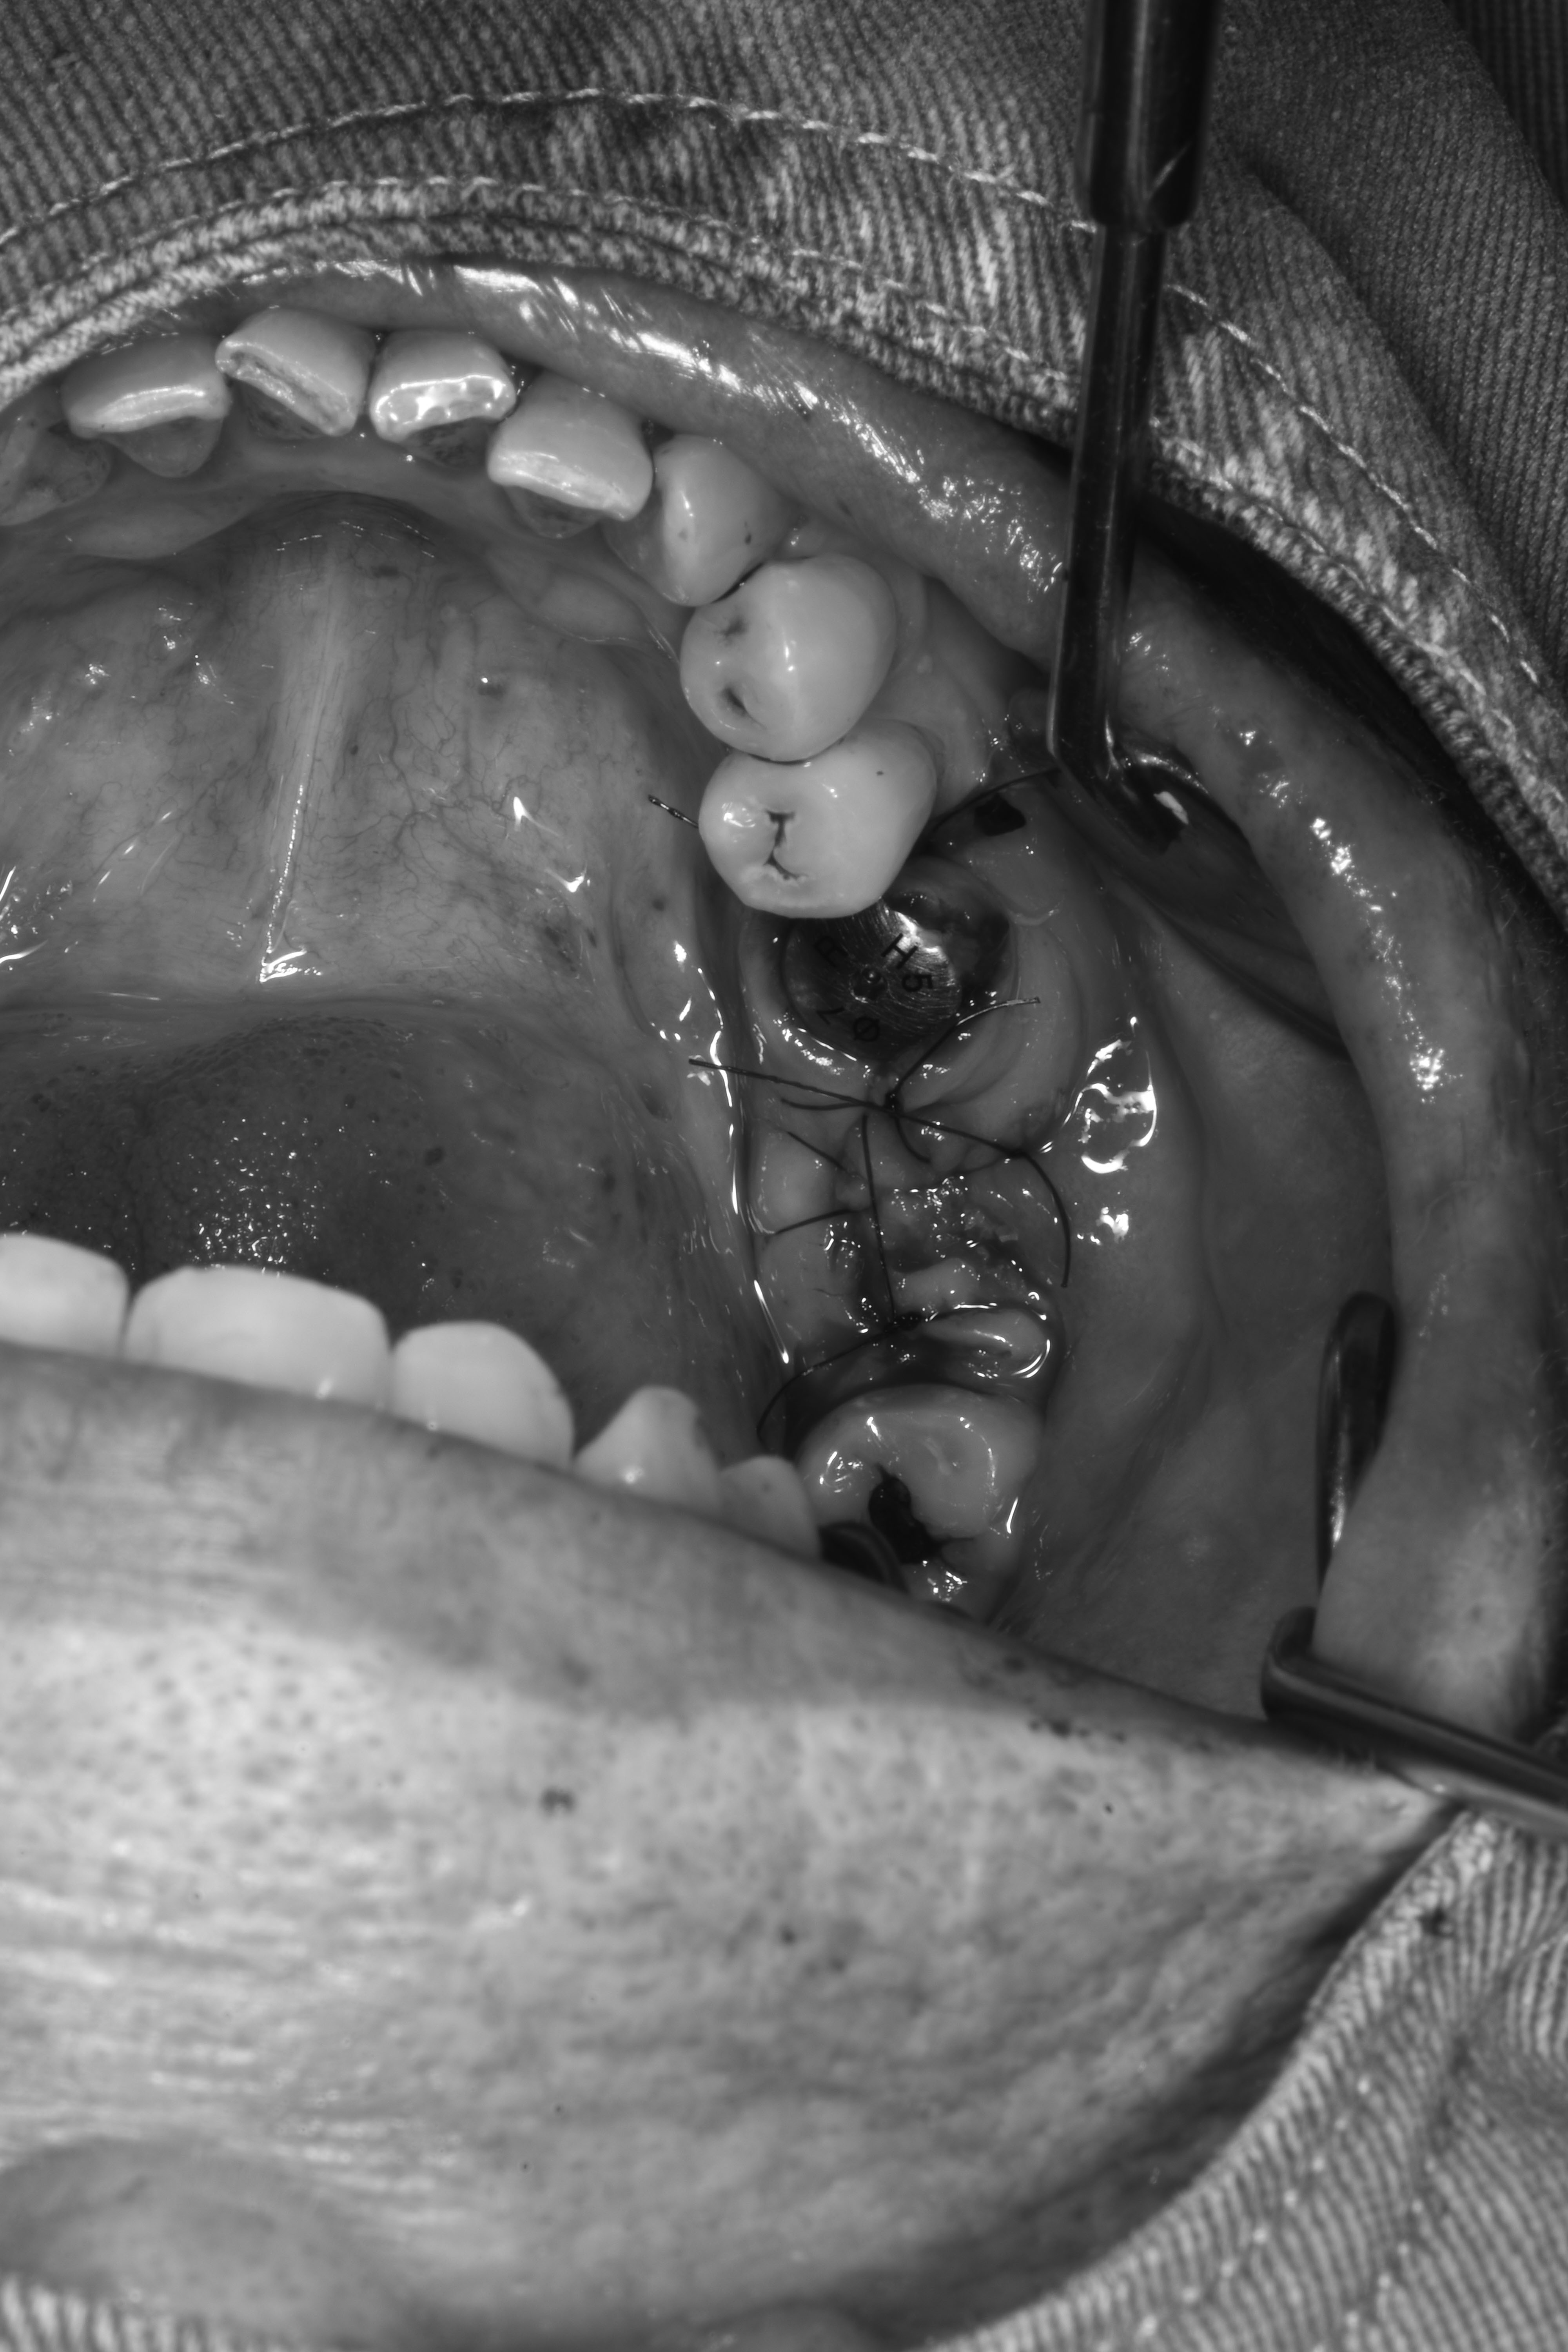

牙齦移植術(補肉)

齒槽骨保存術(拔完牙立即補骨)